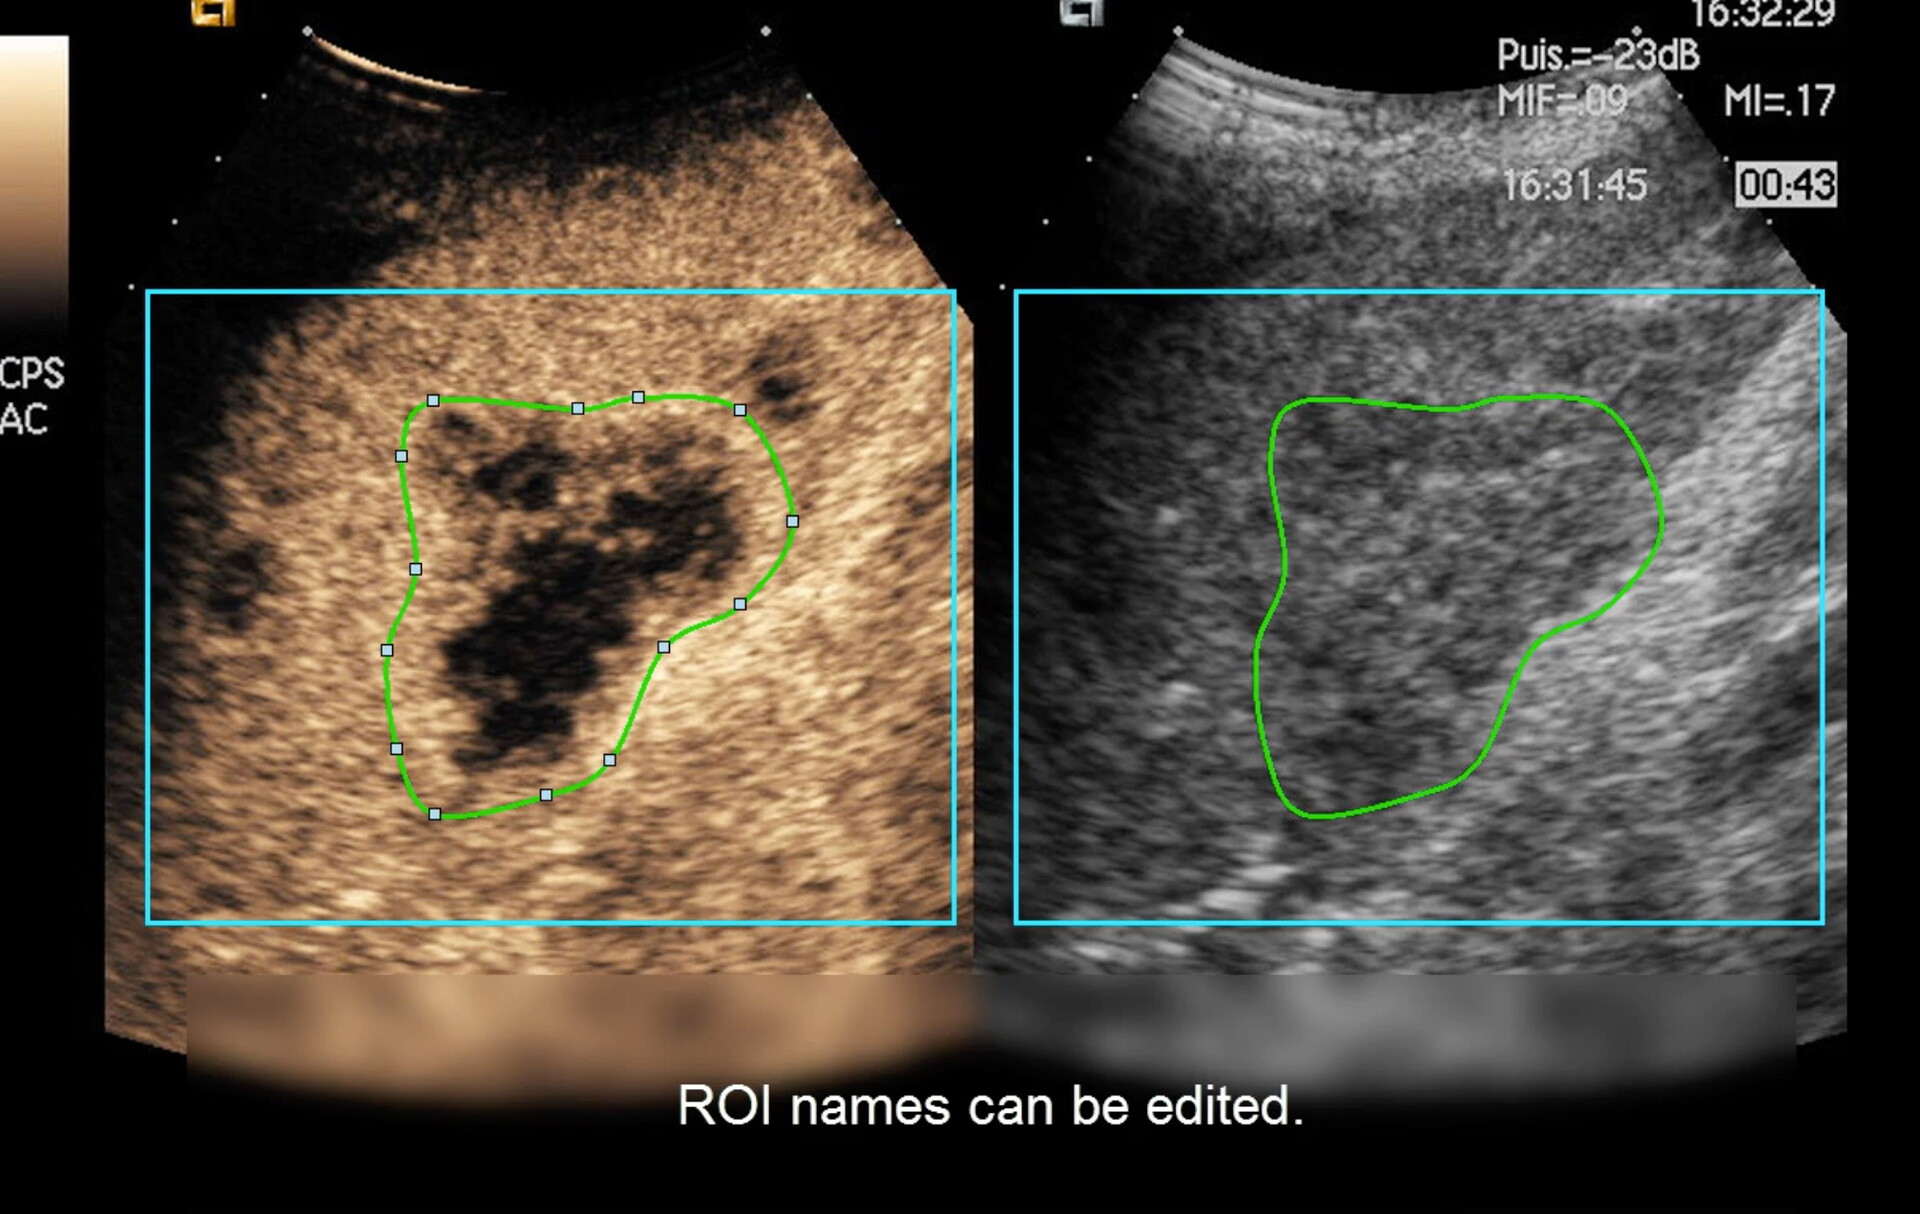

• Saving and retrieving of user-drawn Regions of Interest

• Automatic management of side-by-side display (contrast and B-mode)

• Length and area measurements